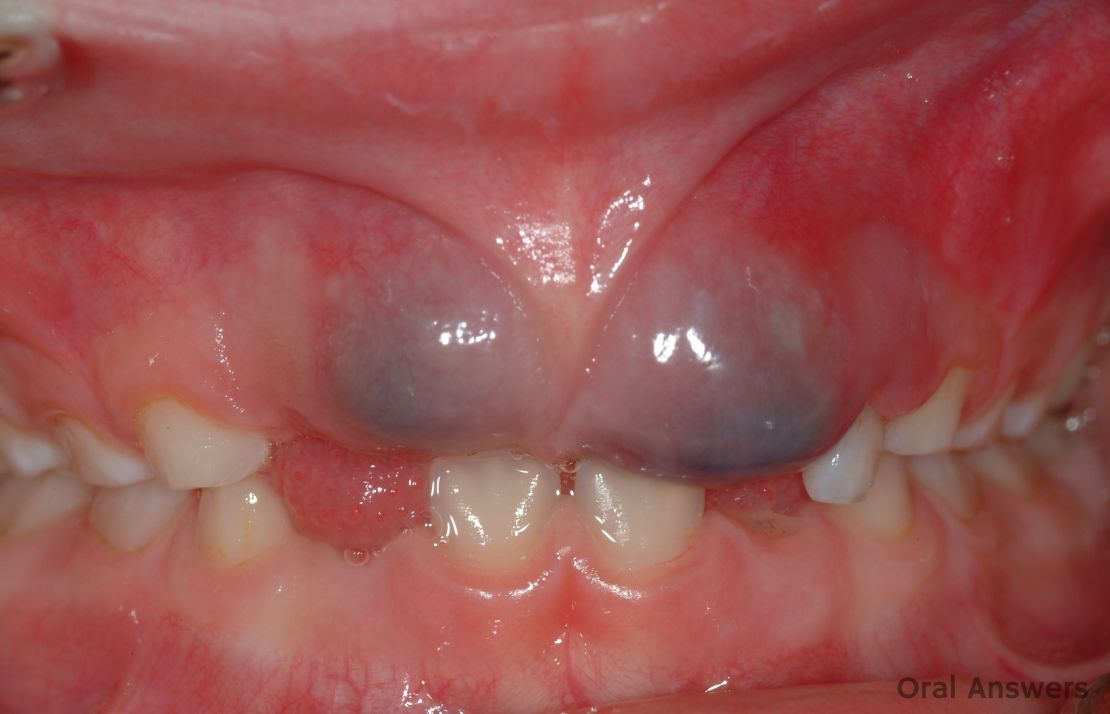

Baby Teething Gum Looks Bruised. Web your baby is born with a full set of teeth below their gums. Finding a lesion, bump, or bruise on your child’s body can be very frightening. Web this causes a bruise to form in the gum tissue between the tooth and the outside surface of your child’s gums. Generally, baby will feel a lot better soon after the tooth has broken through the gum. That said, the larger biting surface of the first molars and second molars means they may also be quite painful and cause the gums to look bruised during molar teething. Sometime during your baby’s first year, these teeth will start to erupt, or break through, their gum line. As a baby’s teeth begin to erupt through the. Web if you're keenly awaiting the arrival of baby's first tooth, there are plenty of things to look out for. Web a teething baby’s eruption cyst is a congenital eruption cyst or a hematoma cyst, depending on the kind of fluid that. Web eruption cysts in teething babies. Be mindful if your baby’s gum looks bruised during teething. Signs baby is teething include swollen,.

Web this causes a bruise to form in the gum tissue between the tooth and the outside surface of your child’s gums. Sometime during your baby’s first year, these teeth will start to erupt, or break through, their gum line. Web eruption cysts in teething babies. Generally, baby will feel a lot better soon after the tooth has broken through the gum. Web if you're keenly awaiting the arrival of baby's first tooth, there are plenty of things to look out for. Finding a lesion, bump, or bruise on your child’s body can be very frightening. Web a teething baby’s eruption cyst is a congenital eruption cyst or a hematoma cyst, depending on the kind of fluid that. Signs baby is teething include swollen,. As a baby’s teeth begin to erupt through the. Web your baby is born with a full set of teeth below their gums.

Baby Teething Gum Looks Bruised Be mindful if your baby’s gum looks bruised during teething. Signs baby is teething include swollen,. Generally, baby will feel a lot better soon after the tooth has broken through the gum. Web your baby is born with a full set of teeth below their gums. That said, the larger biting surface of the first molars and second molars means they may also be quite painful and cause the gums to look bruised during molar teething. Finding a lesion, bump, or bruise on your child’s body can be very frightening. Web this causes a bruise to form in the gum tissue between the tooth and the outside surface of your child’s gums. Web a teething baby’s eruption cyst is a congenital eruption cyst or a hematoma cyst, depending on the kind of fluid that. Web if you're keenly awaiting the arrival of baby's first tooth, there are plenty of things to look out for. Be mindful if your baby’s gum looks bruised during teething. Web eruption cysts in teething babies. Sometime during your baby’s first year, these teeth will start to erupt, or break through, their gum line. As a baby’s teeth begin to erupt through the.